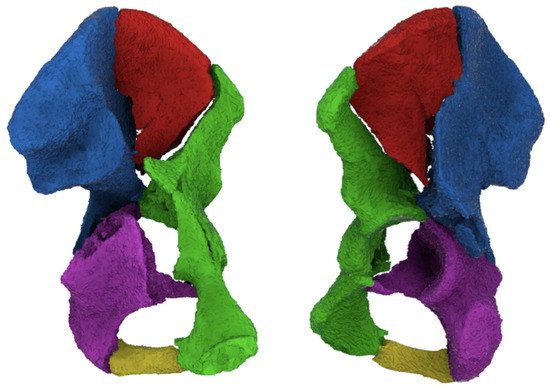

A ‘2D survey’ was generated to gain knowledge on how both-column acetabular fractures are currently treated. First, the surgeons were asked to answer a few general questions regarding their experience with pelvic surgery. They were asked (1) how many years of experience they have with pelvic surgery, and (2) how many acetabular fractures they operate on in a year. Next, they were asked to judge fifteen cases. For each case, basic patient information (gender and age), pelvic radiographs (anteroposterior (AP) overview (Figure 1a)), and 2DCT images (axial, coronal, and sagittal views (Figure 1b–d)) were provided. The images were retrieved from the electronic health record as DICOM images, were anonymized in Mimics Medical version 19.0 (Materialise, Leuven, Belgium), and uploaded to dicomlibrary: an online medical DICOM image file sharing service for educational and scientific purposes. It was possible to scroll through the CT slices and perform measurements in this viewer. For each case, the surgeons were asked to elaborate on which treatment they would recommend for the shown fracture: Nonoperative, Open Reduction and Internal Fixation (ORIF), or primary Total Hip Arthroplasty (THA). Surgeons were asked which surgical approach they would recommend when performing the surgery: anterior approach (either a Modified Stoppa approach possibly with a lateral window or an ilioinguinal approach), posterior approach (a Kocher–Langenbeck approach possibly with a trochanter osteotomy), or a combined approach (anterior as well as posterior), if ORIF was chosen. Finally, the level of confidence of the surgeon in the chosen treatment strategy (e.g., conservative versus operative and surgical approach) was given on a scale from 0 to 100 (zero indicating no confidence at all and one hundred as having full confidence).

Figure 1. Conventional imaging provided within the surveys: (a) pelvic radiograph (AP overview), (bd) examples of the axial, coronal, and sagittal CT slice (surgeons could scroll through every slice of the CT scan).